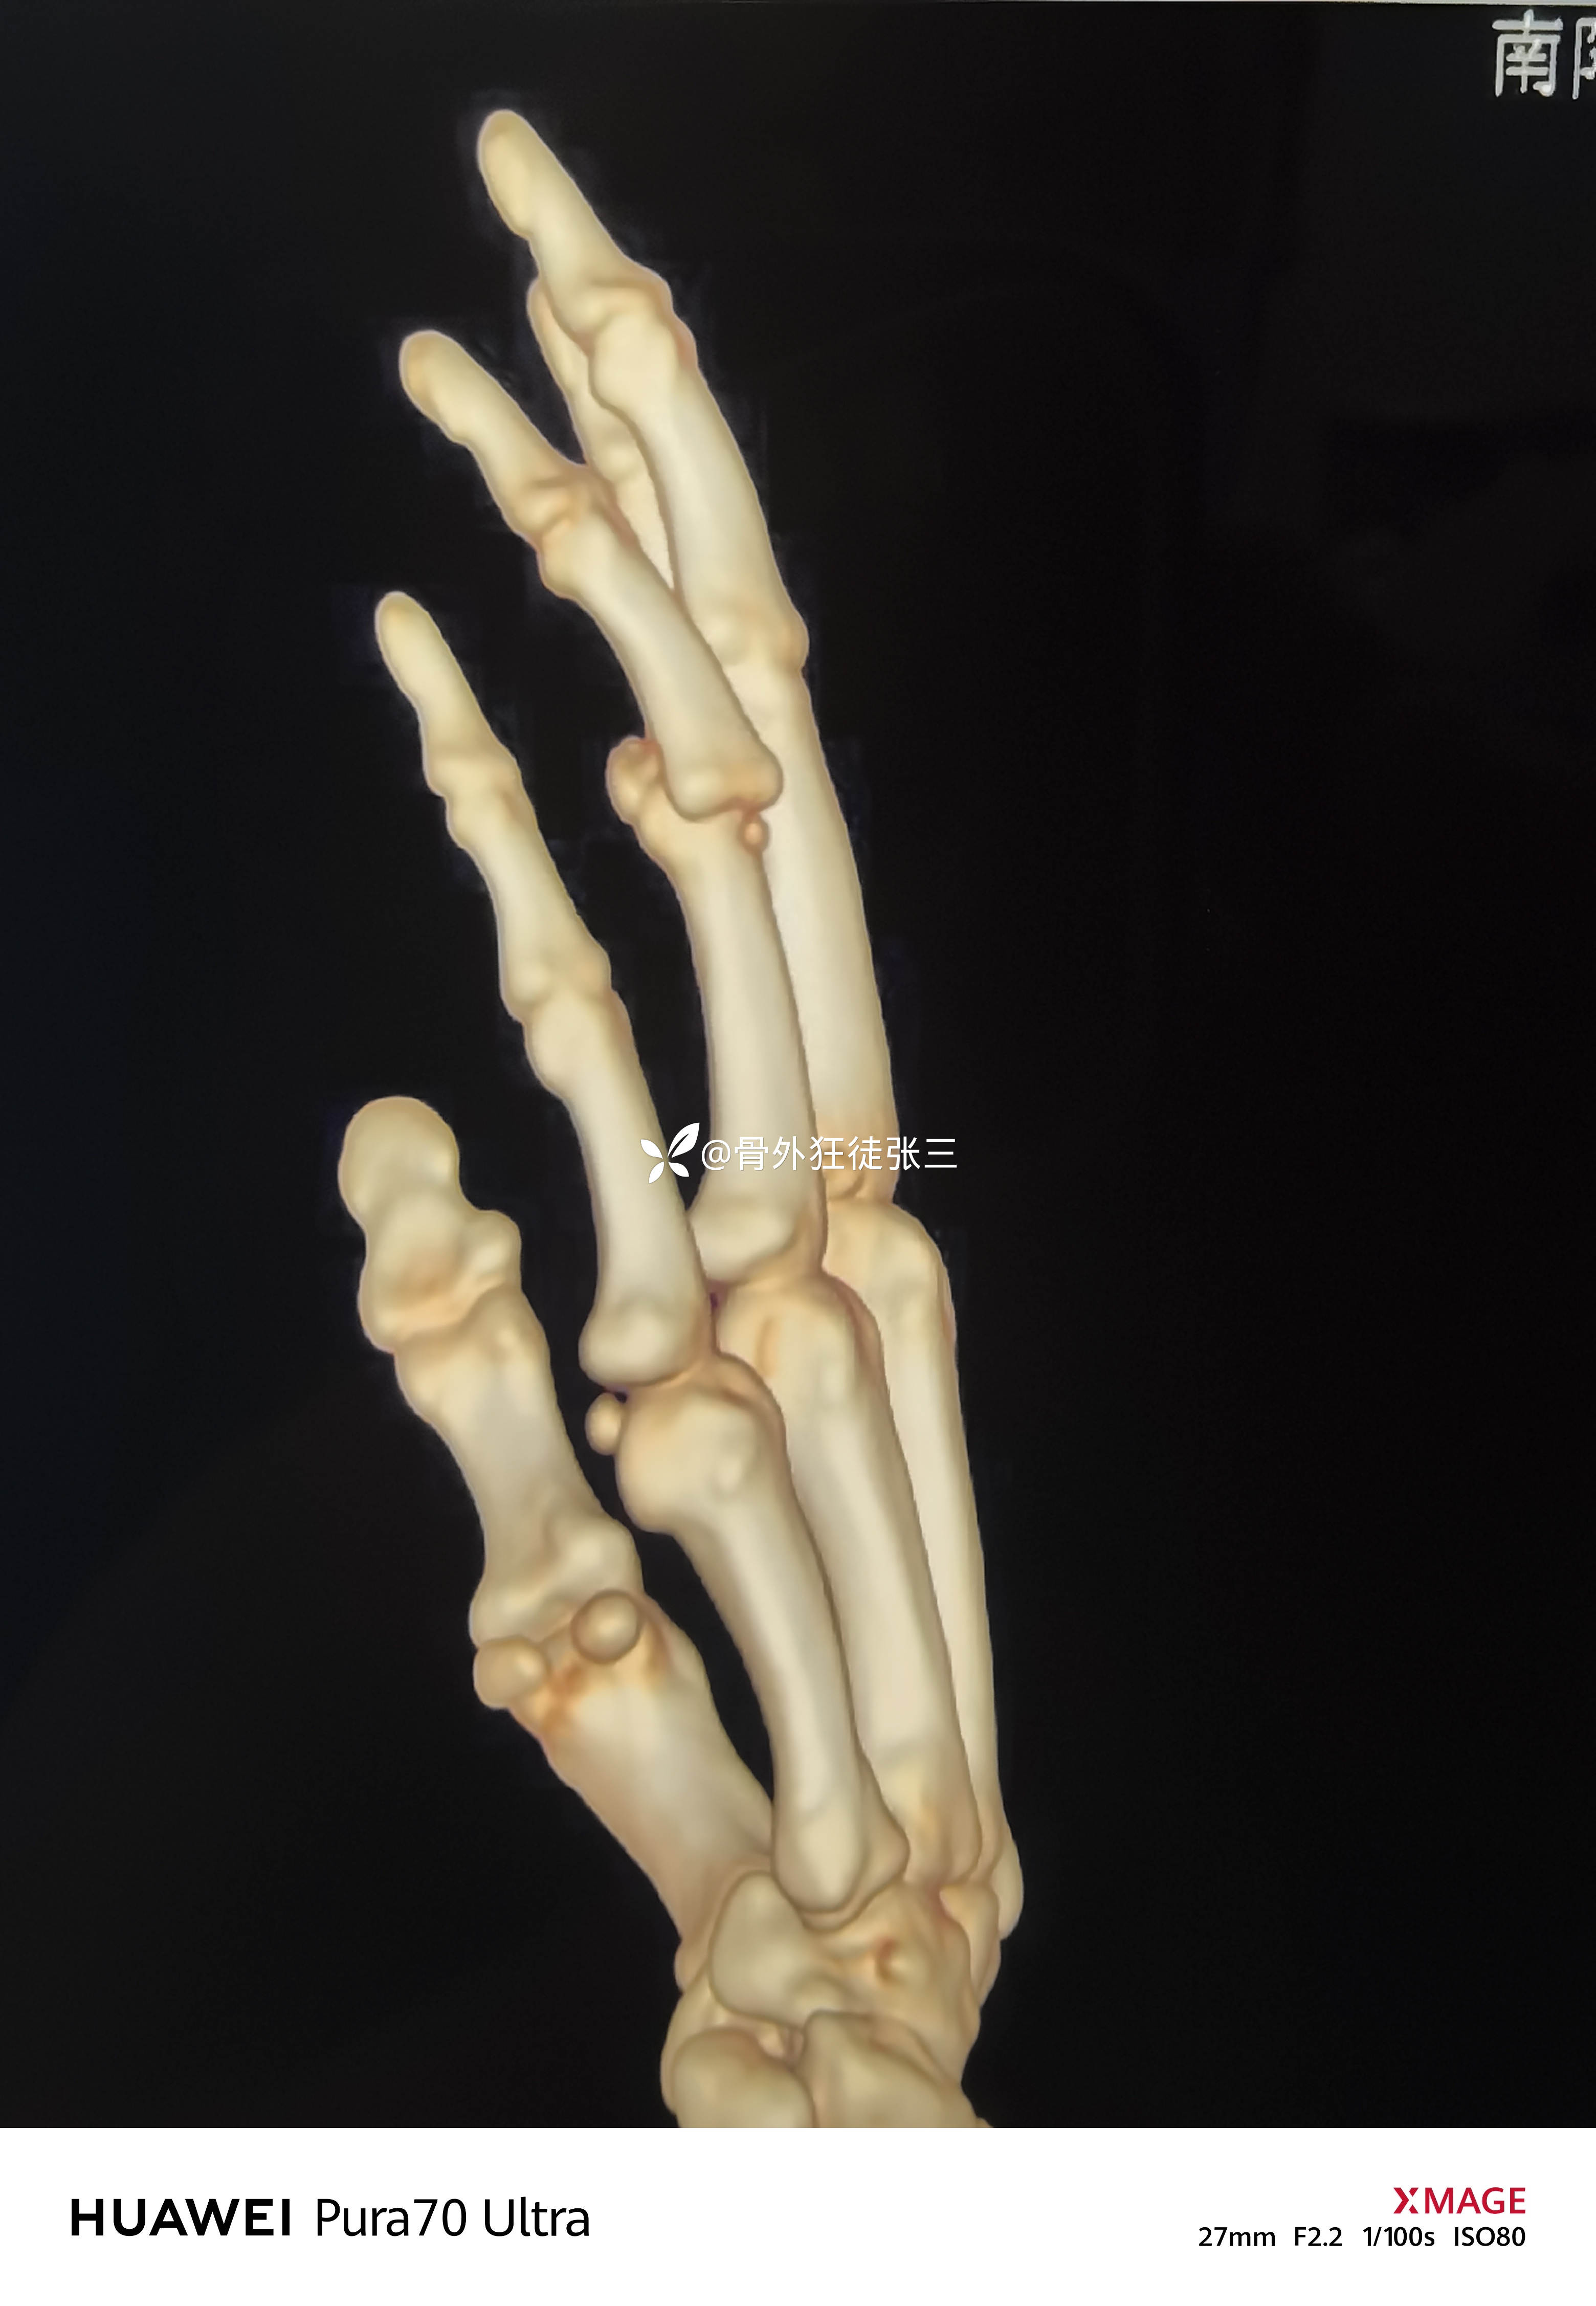

X线显示近指间关节后脱位

中节指骨基底掌侧浅屈肌腱止点骨折

左手环指中节指骨Pilon骨折